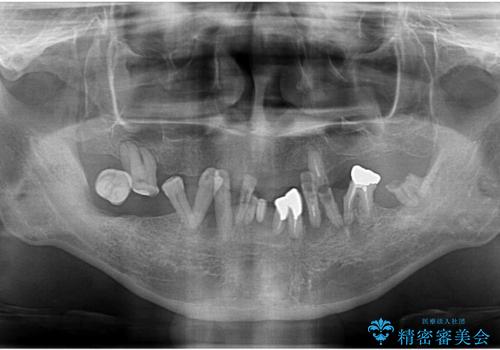

全体的に治したい。インプラントオーバーデンチャーによる治療。

- 見た目を治したい。全体的に治したいとの事で来院。

保存できる歯がなかったので全て抜歯をし、インプラントを埋入し、磁性アタッチメントを用いたインプラントオーバーデンチャーで治療を行いました。